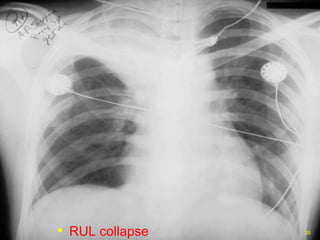

RUL collapse